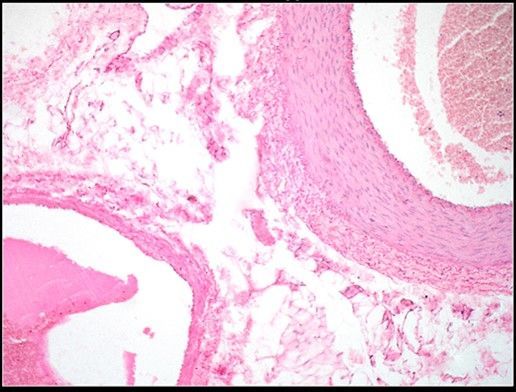

Question 10

Question

Label this image

Image:

b3eefebb-49dc-47b8-bc6b-0334a1c16f94 (image/jpeg)

Answer

Tonsils